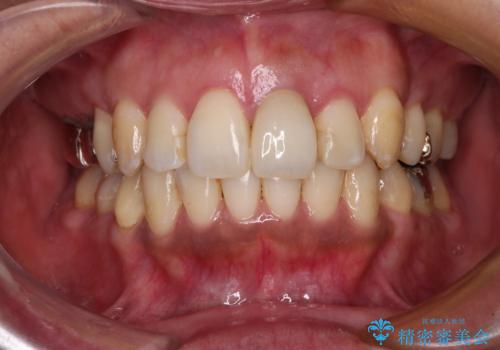

- 下顎前歯が痛んで近医を受診したところ、下顎前歯2本を抜歯してインプラント治療が必要と診断されたとのことで来院された患者様です。

診査の結果、下顎左側中切歯の神経が失活していることが痛みの原因であり、根管治療を行う必要があると診断されました。

根管治療を行った後にオールセラミッククラウンにて補綴することとしました。

隣在歯にも根尖部の炎症が及んでいるように見えましたが、術前診査では神経が失活している様子がなかったため、まずは原因歯から処置を行うこととしました。

初回の根管治療後には痛みが速やかに改善し、6か月後のレントゲン写真では根尖の病変が消失していることが確認できました。